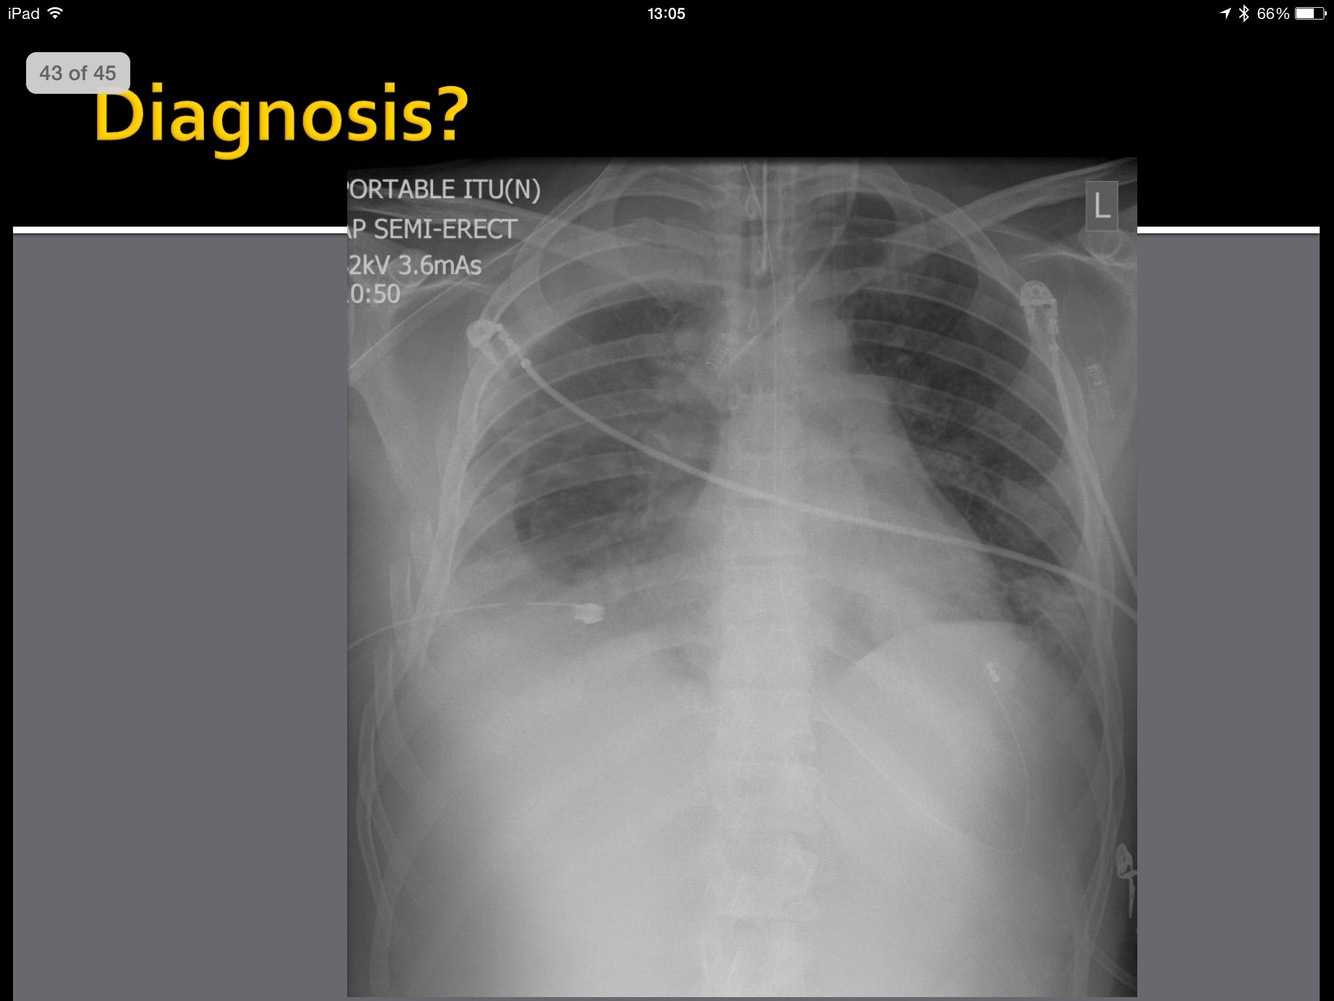

What is the pathology here?